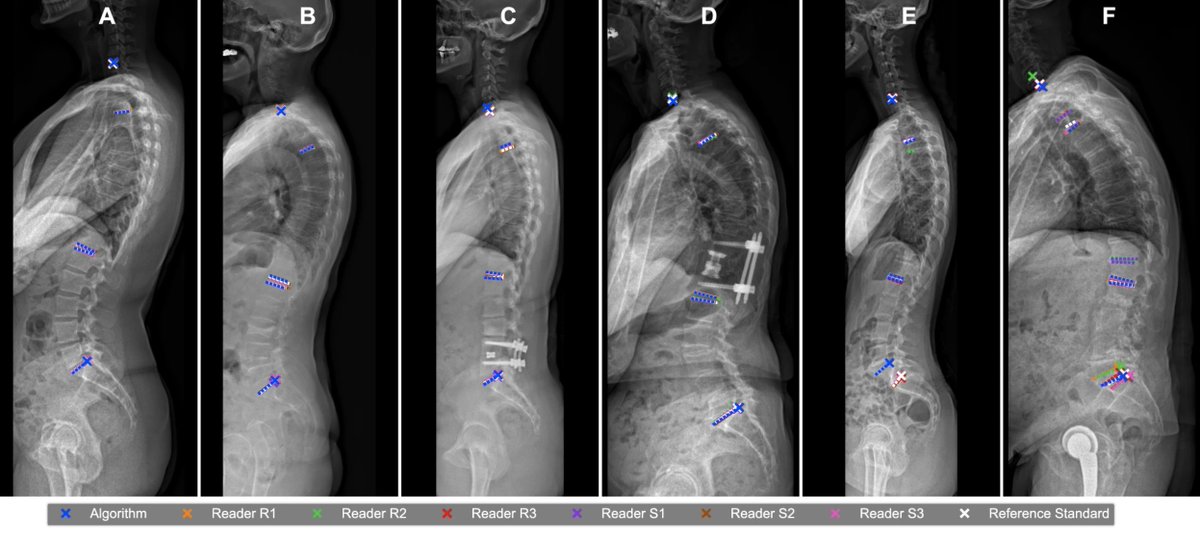

Hoppe et al. show that automated #Spinopelvic measurements on #Radiographs with #AI are accurate within the variability of experienced readers, but with the potential to save time and increase reproducibility. #LMUradiology doi.org/10.1007/s11547…

Hoppe et al. show that automated #Spinopelvic measurements on #Radiographs with #AI are accurate within the variability of experienced readers, but with the potential to save time and increase reproducibility. #LMUradiology

doi.org/10.1007/s11547…